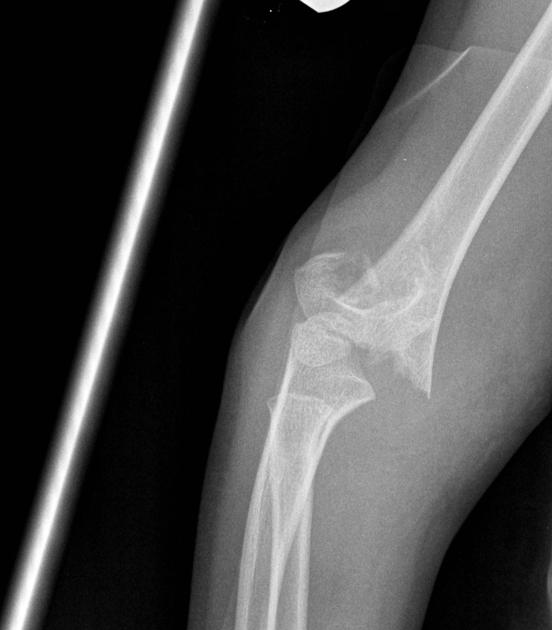

[toggle title=”Ön ve Arka Yağ Yastıkçığı Bulgusu” state=”close”]

Normalde eklem kapsülünde yağ yastıkçıkları bulunur.

Anterior yağ yastıkçığı koronoid fossada bulunur ve normal grafide de ince bir çizgi halinde görülebilir. Ancak anterior yağ yastıkçığı ayrışmış ve daha belirginleşmişse buna Yelken Bulgusu (Sail sign) denir ve görülmesi patolojiktir.

Olekranon fossada bulunan posterior yağ yastıkçığının grafide görülmesi ise her zaman patolojiktir.

Bazı non-deplase kırıklarda kırık hattı görülemeyebilir ve anormal yağ yastıkçığı işareti yaralanmanın tek bulgusu olabilir.

Travma öyküsü olan hastalarda yağ yastıkçığı görülmesi aksi kanıtlanana kadar kırığa sekonder düşünülmelidir.